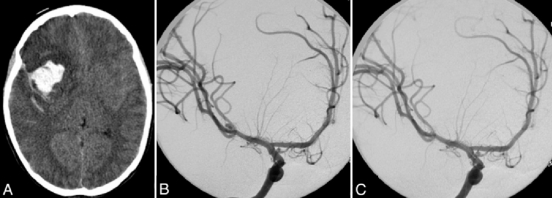

远端小脑前下动脉(AICA)瘤非常罕见。大多数远端小脑前下动脉瘤因蛛网膜下腔出血而出现症状。...

剧烈的头痛骤然而来,随后意识逐渐模糊,直至陷入昏迷。一切来得太急,快到家人根本来不及反应,整个家庭就这样被猛地推进了恐惧之中。到医院检查后,噩耗接踵而至:颅内大出血,原因是...